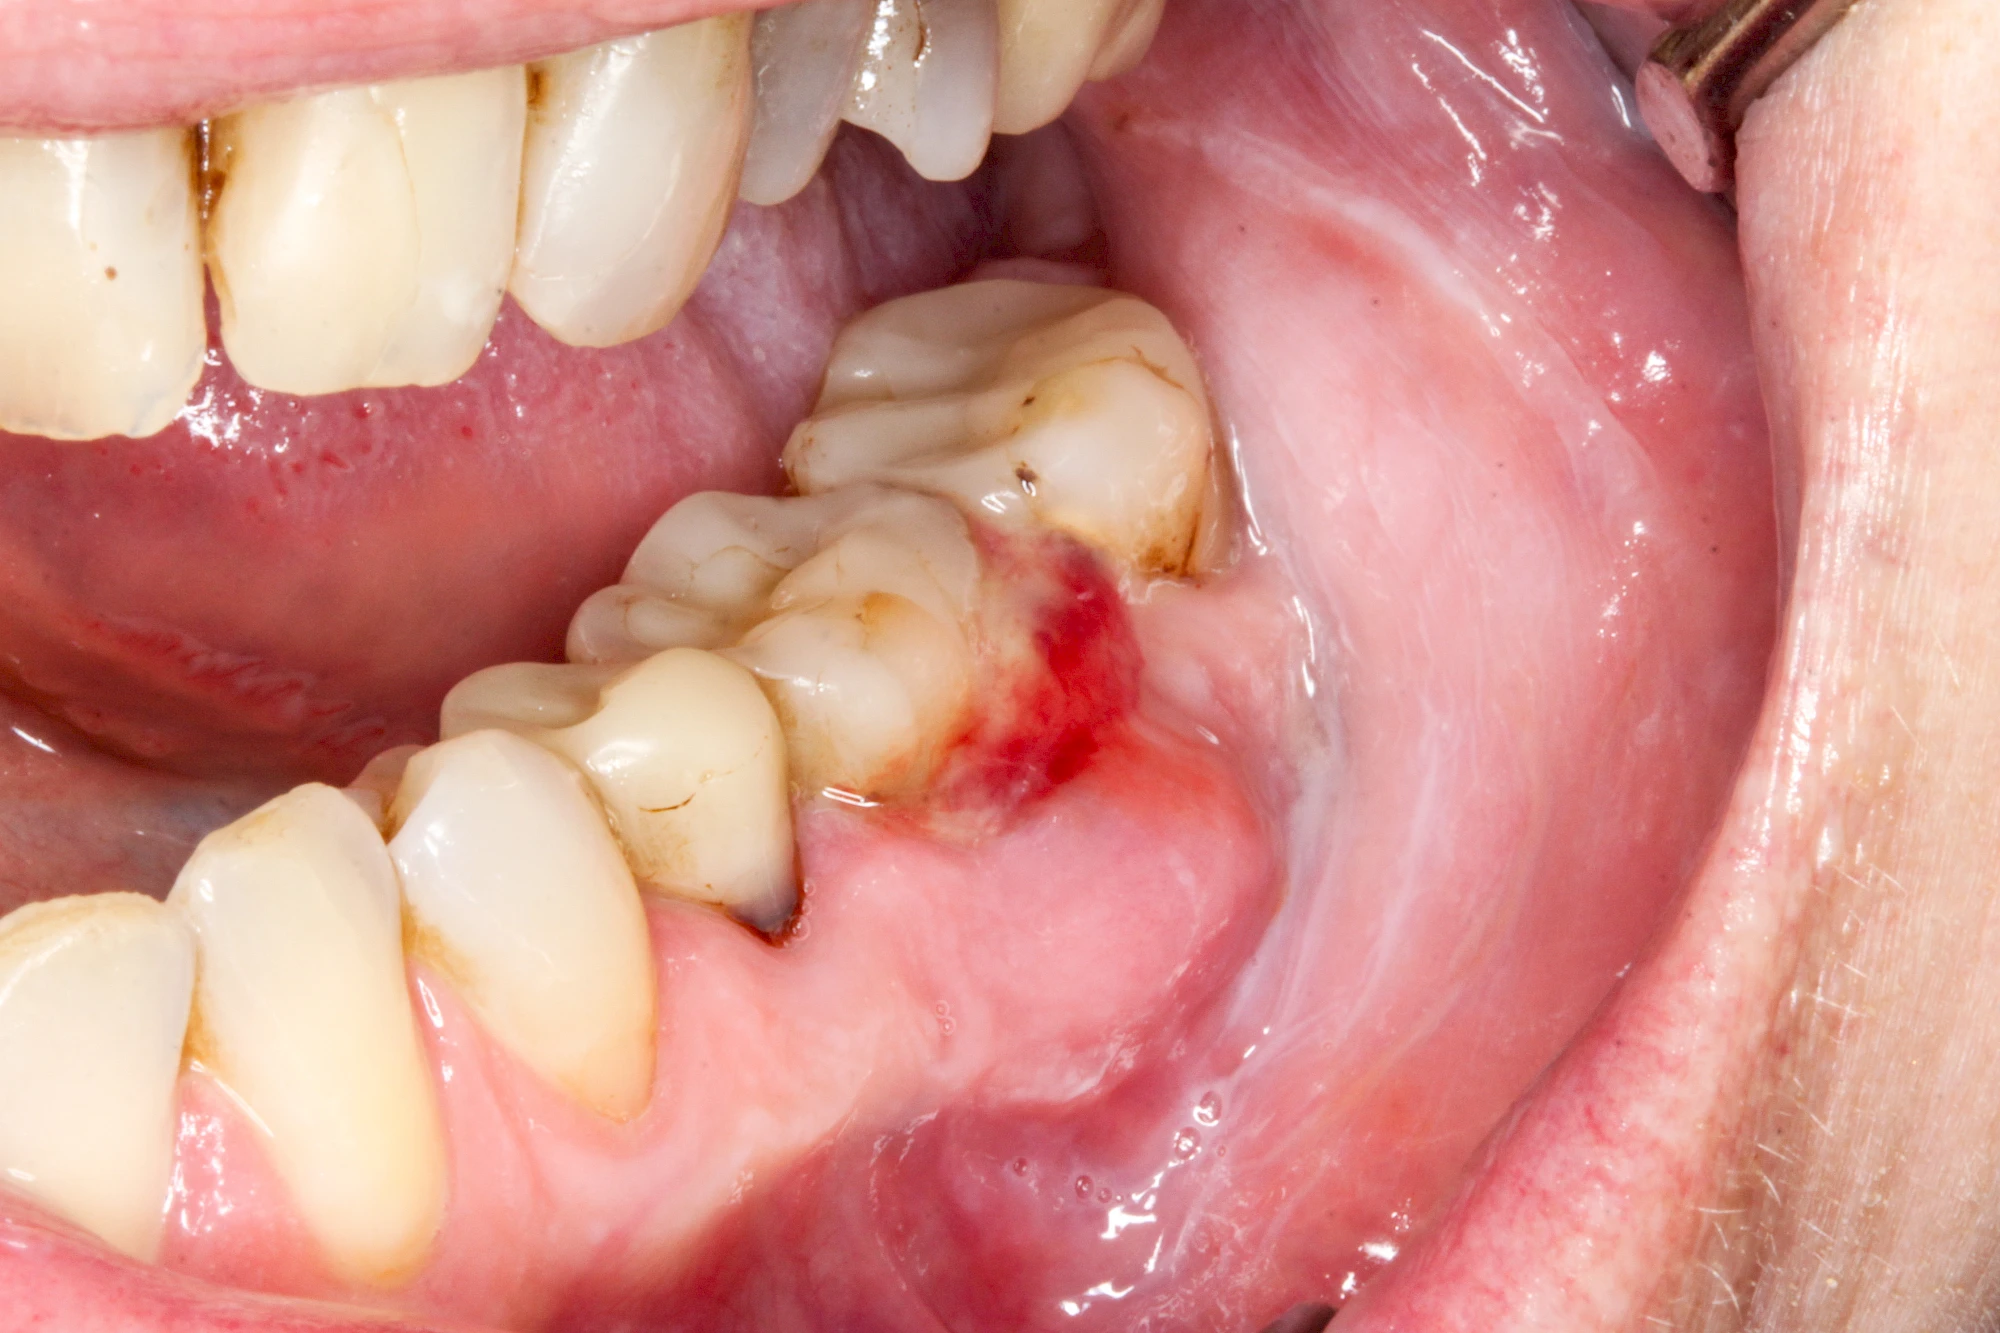

Im Laufe der menschlichen Entwicklung haben sich die Kiefer aufgrund unserer Nahrungsumstellung rückgebildet. Die Weisheitszähne haben daher oft keinen Platz mehr. Bei ca. 30 % der Menschen sind diese Zähne schon gar nicht mehr angelegt. Zum Teil liegen die Zähne versteckt (retiniert) im Kiefer und sind nicht sichtbar. Hin und wieder brechen die Zähne zwar durch die Schleimhaut, aber nicht vollständig – es handelt sich um einen erschwerten Zahndurchbruch (dentitio difficilis). Dann sind die Zähne noch teilweise bedeckt von einer "Schleimhautkapuze". Gehen hier Speisereste und Bakterien unter die Schleimhautkapuze kann sich eine sogenannte Schlupfwinkelinfektion bilden. Diese Entzündungen treten spontan auf, sind häufig sehr schmerzhaft und die Mundöffnung ist eingeschränkt. Hier ist umgehend der Zahnarzt zu kontaktieren.